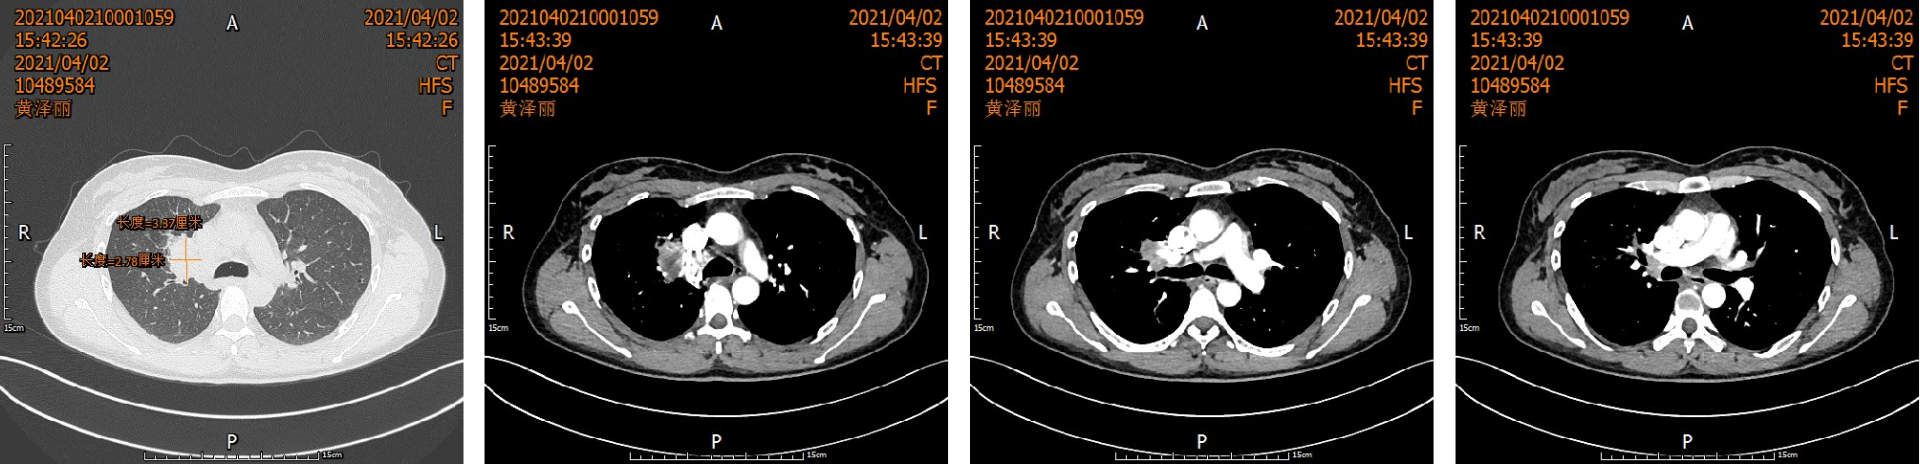

5年前,一位40岁的母亲因"咳血三月"到胸心外科就诊。CT结果显示:右上肺门区肿块,支气管粘液栓。活检确诊为非小细胞肺癌(T3NxM0)。

患者术前影像